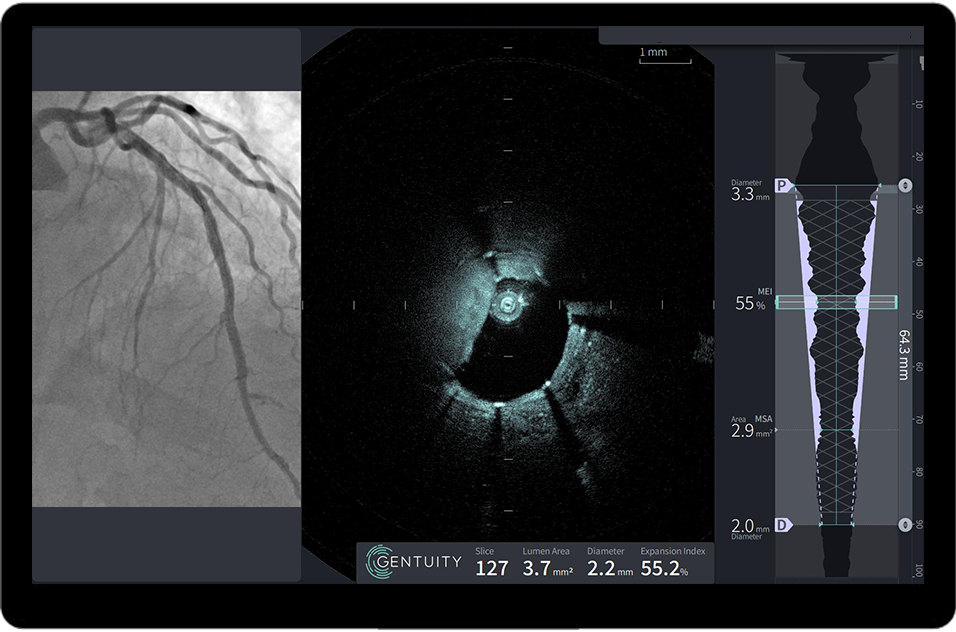

HF-OCT Imaging System and Vis-Rx® PRIME

Micro-Imaging Catheter

Discover how high-frequency OCT technology helps physicians visualize coronary anatomy and guide confident treatment decisions

HF-OCT is designed to give interventional cardiologists vessel insight before PCI. By visualizing plaque characteristics, vessel size, and lesion morphology, it supports informed treatment planning, with a system designed for fast setup and easy use in the cath lab.

AI-powered analysis

Automated measurements and stent analysis provide real-time guidance, supporting rapid and informed decision-making.

HF-OCT–Guided PCI in a Critically Narrow LAD

Vis-Rx crosses and clears an LAD lesion with a tight, heavily calcified MLA of 0.3mm2